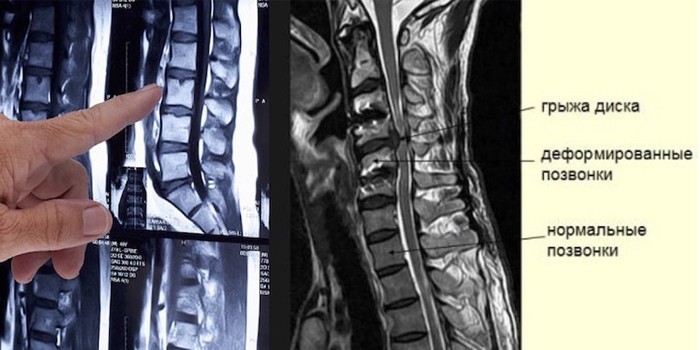

- Магнитно-резонансную томографию (МРТ). Метод основан на измерении отклика атомных ядер, для возбуждения которых используют электромагнитные волны. С помощью МРТ получаются четкие снимки труднодоступных органов, связок, мышц, можно измерить скорость кровотока, спинномозговой жидкости. Метод дает более четкие кадры, чем УЗИ, но его нельзя делать людям, у которых в теле металлические предметы (кардиостимуляторы, протезы, пирсинг).

- межпозвонковую грыжу;